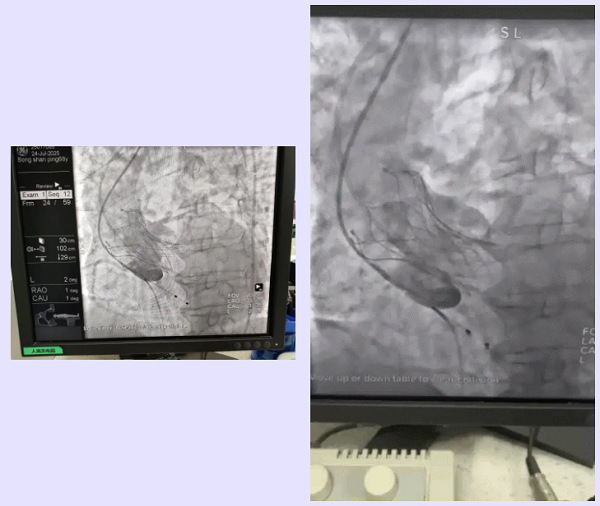

术中,团队凭借精湛技术与默契协作,成功将一枚30mm的微创可回收人工生物瓣膜精准输送至病变的主动脉瓣位置并释放。术后即刻评估显示:跨主动脉瓣压差显著降至1 mmHg;患者血流动力学得到根本性改善;冠脉血流灌注良好,无相关并发症。

▲术中关键步骤造影图像